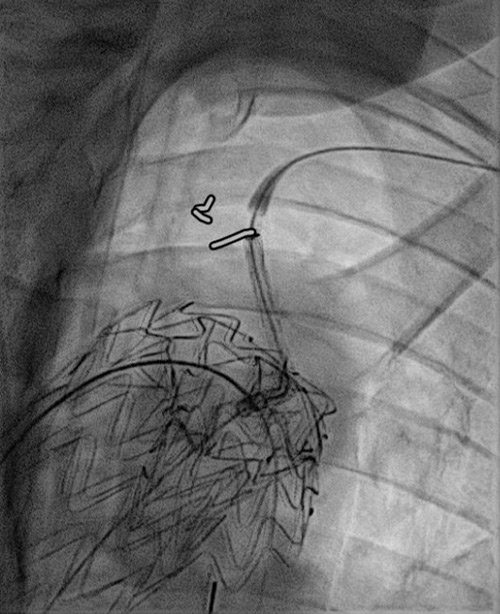

GORE® TAG® Thoracic Branch Endoprosthesis (TBE)

Challenging branch take-offs may require specific angulations!

Step 1: result